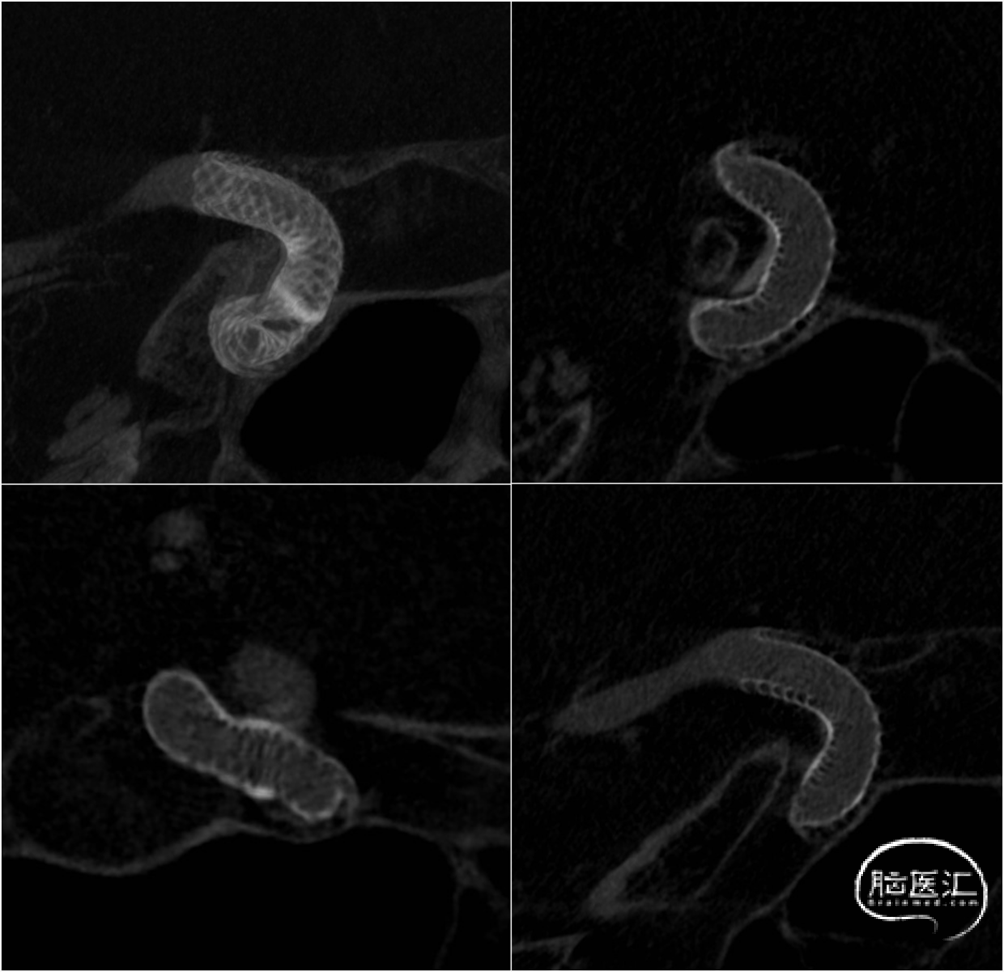

男性,71岁,体检发现颅内动脉瘤,位于颈内动脉眼段,形态不规则。

侧壁囊性动脉瘤,目前的主流方式是FD,本例动脉瘤直径较小,不必辅助弹簧圈。患者年龄较大,动脉硬化程度较重,围术期出现缺血并发症的风险略高,且抗栓治疗效果一般,AA抑制率91%,ADP抑制率45%;增强抗栓效果又恐引起其它脏器的出血,因此选择经过表面修饰,自带抗栓属性的新一代FD,Pipeline Shield应为上策。